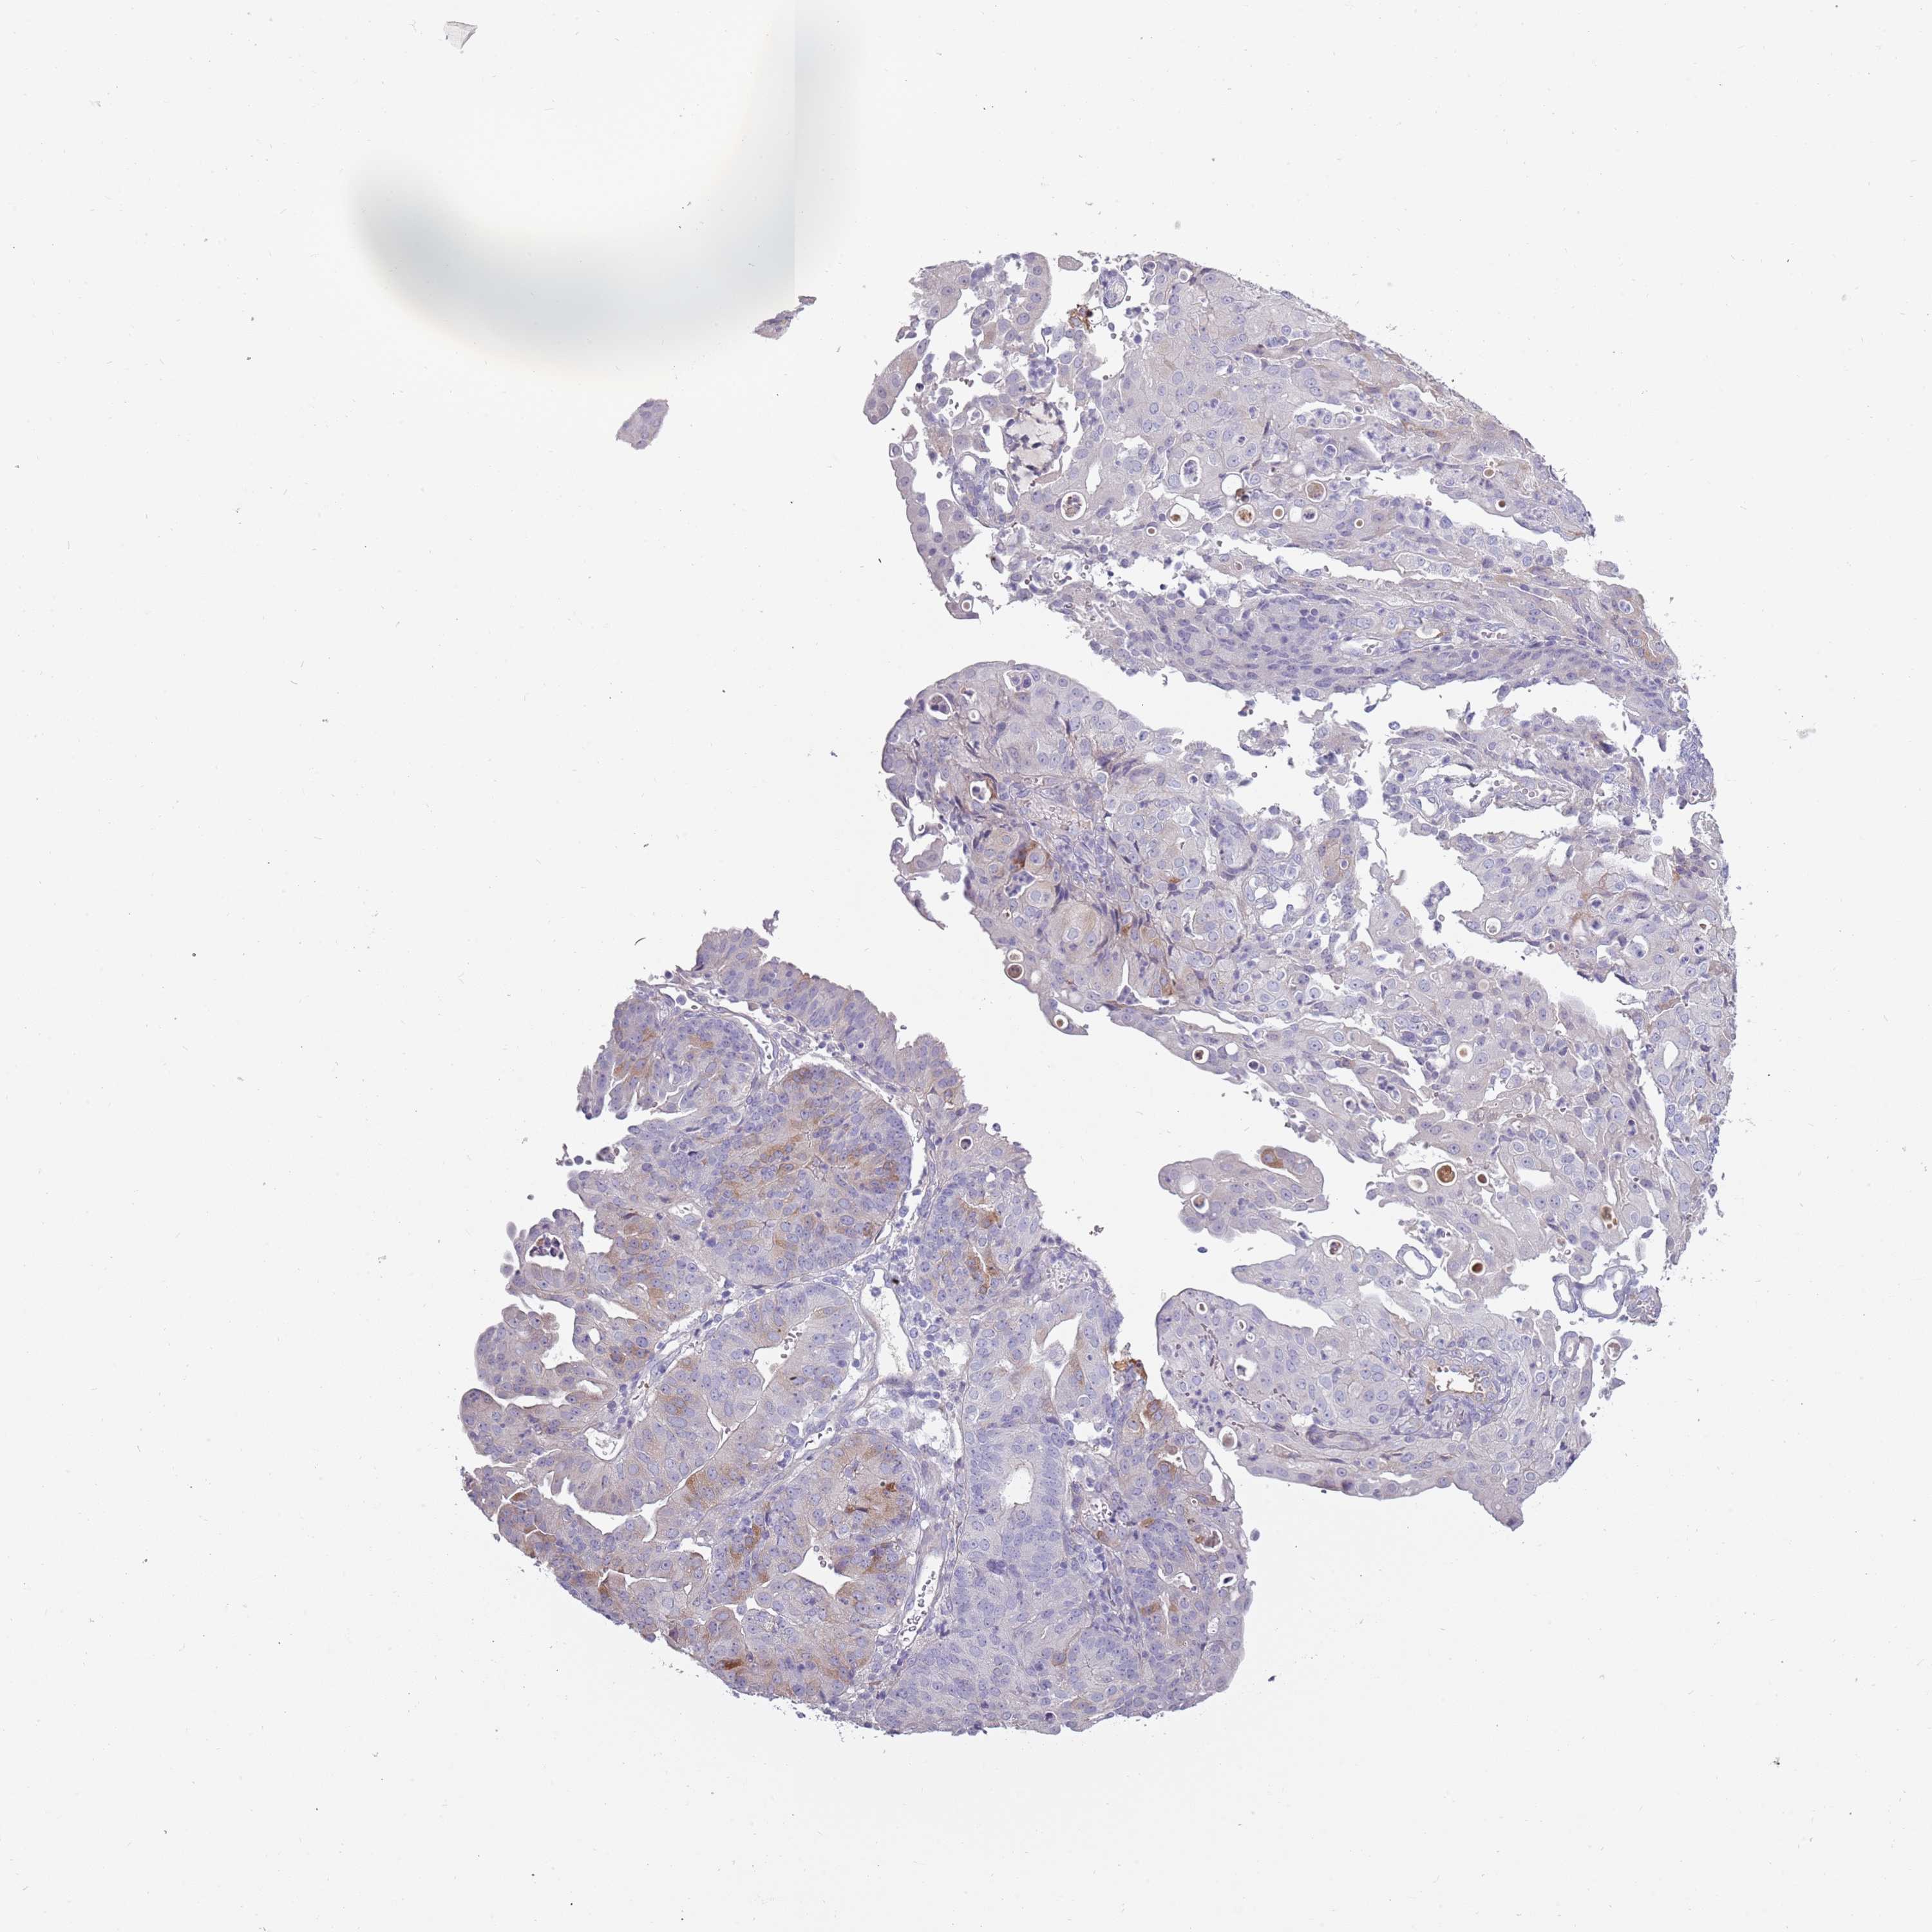

ENDOMETRIAL CANCER - Protein expressioni

A mouse-over function shows sample information and annotation data. Click on an image to view it in a full screen mode. Samples can be filtered based on level of antibody staining by selecting one or several of the following categories: high, medium, low and not detected. The assay and annotation is described here.

Note that samples used for immunohistochemistry by the Human Protein Atlas do not correspond to samples in the TCGA dataset.

Antibody stainingi

Antibody staining in the annotated cell types in the current human tissue is reported as not detected, low, medium, or high, based on conventional immunohistochemistry profiling in selected tissues. This score is based on the combination of the staining intensity and fraction of stained cells.

Each image is clickable and will lead to virtual microscopy that enables deeper exploration of all samples and also displays staining intensity scores, fraction scores and subcellular localization as well as patient and tissue information for each sample.

Antibody HPA047154

Staining

High

Medium

Low

Not detected

Intensity

Strong

Moderate

Weak

Negative

Quantity

>75%

75%-25%

<25%

None

Location

Nuclear

Cytoplasmic/membranous

Cytoplasmic/membranous,nuclear

Adenocarcinoma, NOS